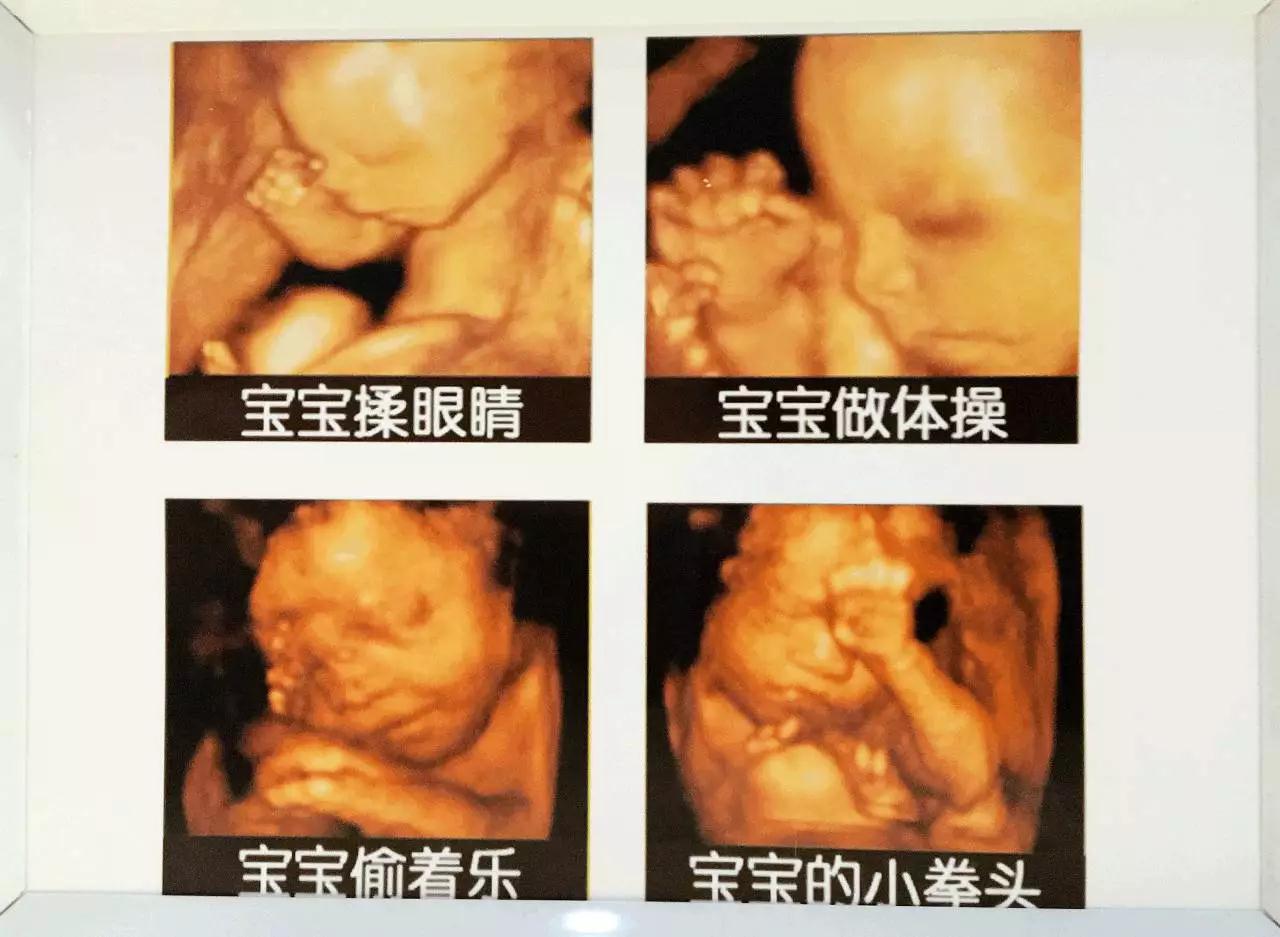

胎宝宝在妈妈肚子里

经过了一段非常奇妙的旅程

胎宝宝在妈妈肚子里的日常